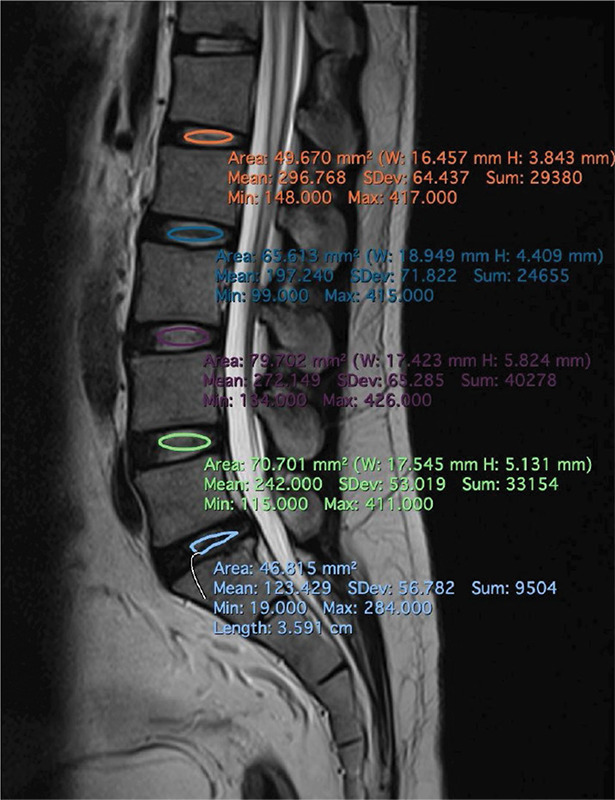

Objectives: This study investigates the relationship between lumbar disc degeneration and sociodemographic factors in a Malaysian cohort, focusing on the diagnostic potential of the disc-cerebrospinal fluid signal ratio (DCFR). With lumbar disc degeneration being a significant cause of low back pain, there is a need for simple yet effective diagnostic measures that are adaptable to diverse imaging conditions. Materials and methods: A retrospective analysis was conducted on 182 patients presenting with low back pain. Magnetic resonance imaging (MRI) was used to assess disc degeneration using the Pfirrmann grading system, while the DCFR was calculated to quantify the severity of disc degeneration. Sociodemographic factors such as age, gender, and race were analyzed for their correlation with degeneration severity and DCFR. Results: The DCFR showed a strong negative correlation with Pfirrmann grades, with older patients and males exhibiting more severe degeneration. Sociodemographic factors significantly influenced degeneration patterns, particularly in the older age groups, with Malays showing a higher prevalence of moderate to severe degeneration. Conclusion: The DCFR provides a consistent and practical quantitative assessment of lumbar disc degeneration. It correlates well with traditional qualitative grading systems and is effective across various age group, making it a valuable tool for clinical and diagnostic applications in diverse populations.